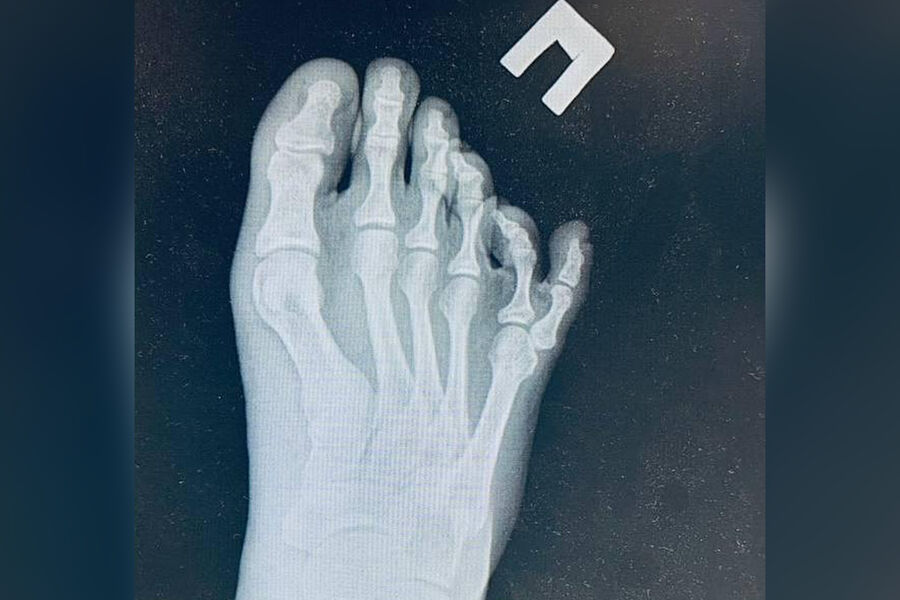

Российские врачи прооперировали школьника с шестью пальцами на ступне

В Подмосковье врачи избавили школьника от шестого пальца на ступне

Врачи Московской областной детской клинической травматолого-ортопедической больницы прооперировали 15-летнего юношу, который страдал полидактилией — патологией, когда человек рождается с лишними пальцами. Об этом сообщили в пресс-службе минздрава Подмосковья.

Школьник много лет испытывал физический и психологический дискомфорт из-за наличия на правой ноге шестого пальца. Медики обследовали подростка и приняли решение об оперативном лечении.

«Врачи провели пациенту реконструктивную операцию, в ходе которой удалили лишний мизинец», — уточнили в ведомстве.